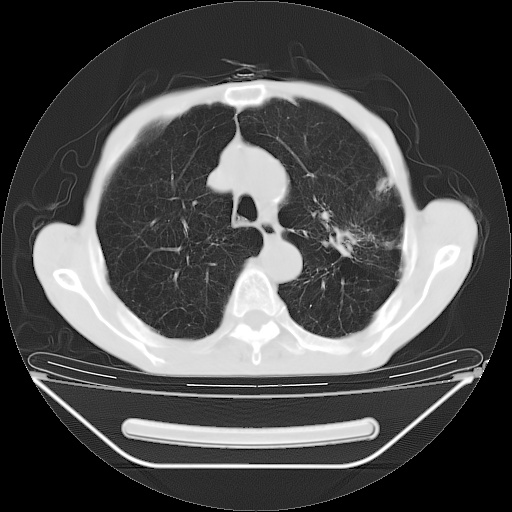

以下是引用zsl6918在2008-8-25 21:55:00的发言:[br]符合右肺周围性肺癌并肺内转移,左肺结核球。双肺肺气肿。腰椎附件转移。

以下是引用随光逐影在2008-8-25 22:03:00的发言:[br]1)考虑右肺下叶周围性肺癌并肺内转移,腰椎附件转移。2)左上肺结核(结核球形成)。3)双肺肺气肿(多发肺大泡形成)。4)双肺门区及纵隔内多发淋巴结钙化。